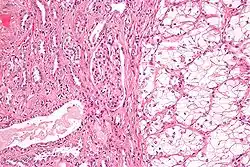

Anatomopathologie

Elle est basée essentiellement sur l'examen anatomopathologique de la pièce chirurgicale d'exérèse, la biopsie n'ayant que peu d'utilité. La classification anatomo-pathologique des tumeurs du rein est la classification UICC.

90 % des cancers du rein sont des carcinomes à cellules rénales, répartis en différents types histologiques[13] :

- Carcinome à cellules claires du rein (80 à 90 %)

- Carcinome papillaire subdivisé en Carcinome papillaire de type 1 et Carcinome papillaire de type 2[24] (10 à 15 %)

- Carcinome à cellules chromophobes (4 à 5 %)

- Carcinome des tubes collecteurs

- Carcinome inclassable